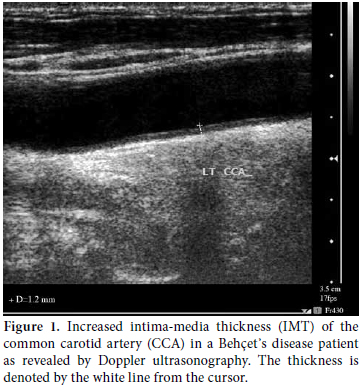

The mean IMT of both the right and left CCA in the BD patients was 0.72±0.4 mm (median 0.6; 0.4-1.8 mm). The carotid IMT was >0.9 mm with atherosclerotic plaque in five patients (16.7%) while no plaque was present in the control group. There were four males (two had autoimmune hepatitis) and one female who tested positive for the hepatitis C virus (HCV) who had hepatomegaly. The US findings in these three patients (with hepatitis) showed focal homogenous echogenic plaque resting on the anterior wall of the common carotid bulb that measured 5x1.8 mm at its maximum dimension in one of the males. The others showed diffuse atherosclerosis of the extracranial carotids. Diffuse IMT of the left CCA with localized plaque on the posterior wall with a lumen reduction of 20% was present in the female. The IMT of the patients with BD was significantly different from what was seen in the control subjects (0.4±0.1 mm) (median 0.4; 0.21-0.6 mm) (p=0.003). Figure 1 shows the US image for increased IMT in one of the patients, and there was no significant difference between smokers and nonsmokers. Furthermore, there was no significant correlation between IMT and BMI.

There was Figure 1: Increased intima-media thickness (IMT) of the common carotid artery (CCA) in a Behçet᾽s disease patient as revealed by Doppler ultrasonography. The thickness is denoted by the white line from the cursor.a significant correlation between IMT and the urea and creatinine (r=0.54, p=0.002 and r=0.42, p=0.02, respectively). It also had a significant positive correlation with cholesterol (r=0.32, p=0.04) and triglycerides (r=0.51, p=0.002), but a negative correlation existed with the high density lipoprotein (HDL) level (r=-0.53, p=0.01). There was a significant correlation between the BDCAF and IMT in BD patients (r=0.42, p=0.02). When comparing the IMT these patients with regard to the presence and absence of arthritis along with the involvement of the central nervous system (CNS) or ocular, there was no significant difference.